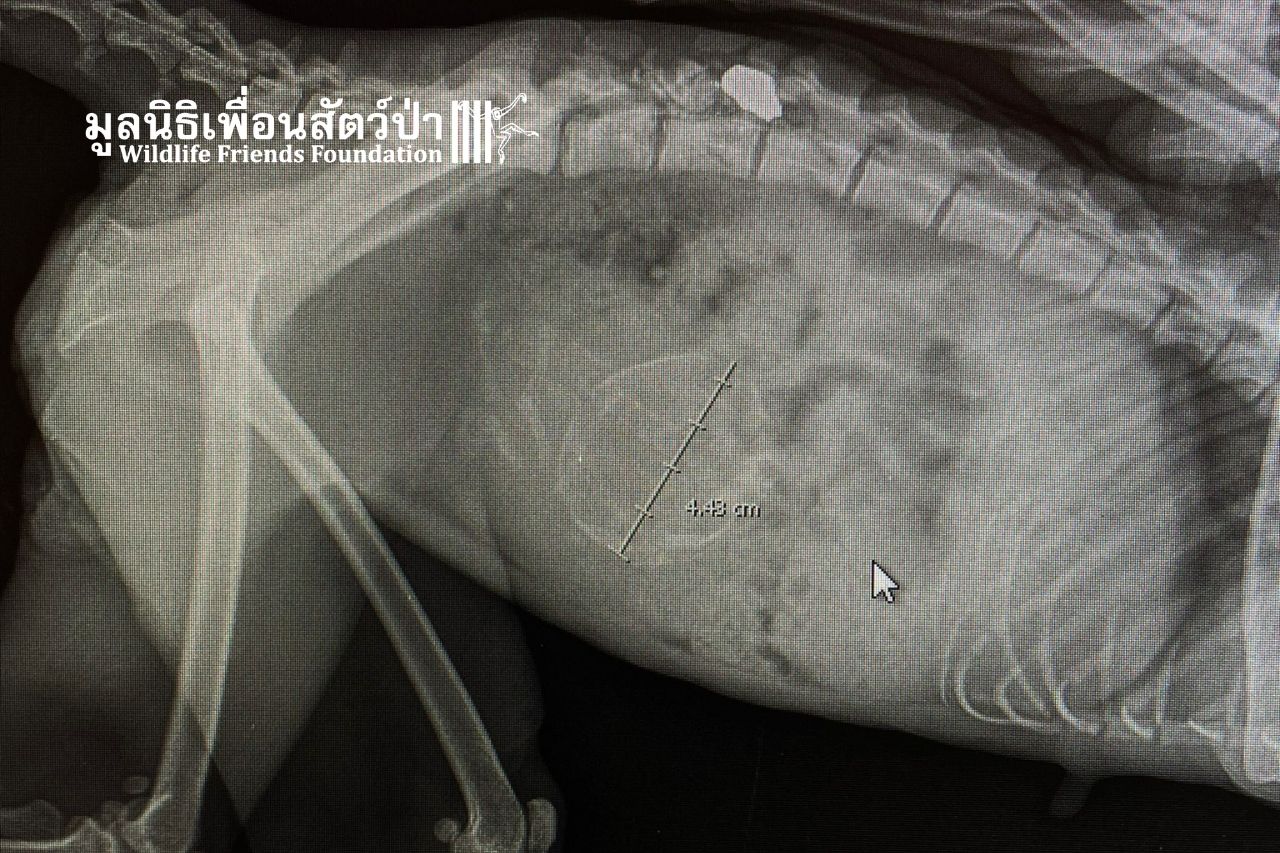

A pregnant female macaque recently arrived at WFFT with a bullet in her spine. Our veterinary team has removed the bullet, but as she is in the late stages of pregnancy, we must monitor her very closely to see if she can deliver on her own, given that we don’t know if she will recover from the damage caused by the bullet.